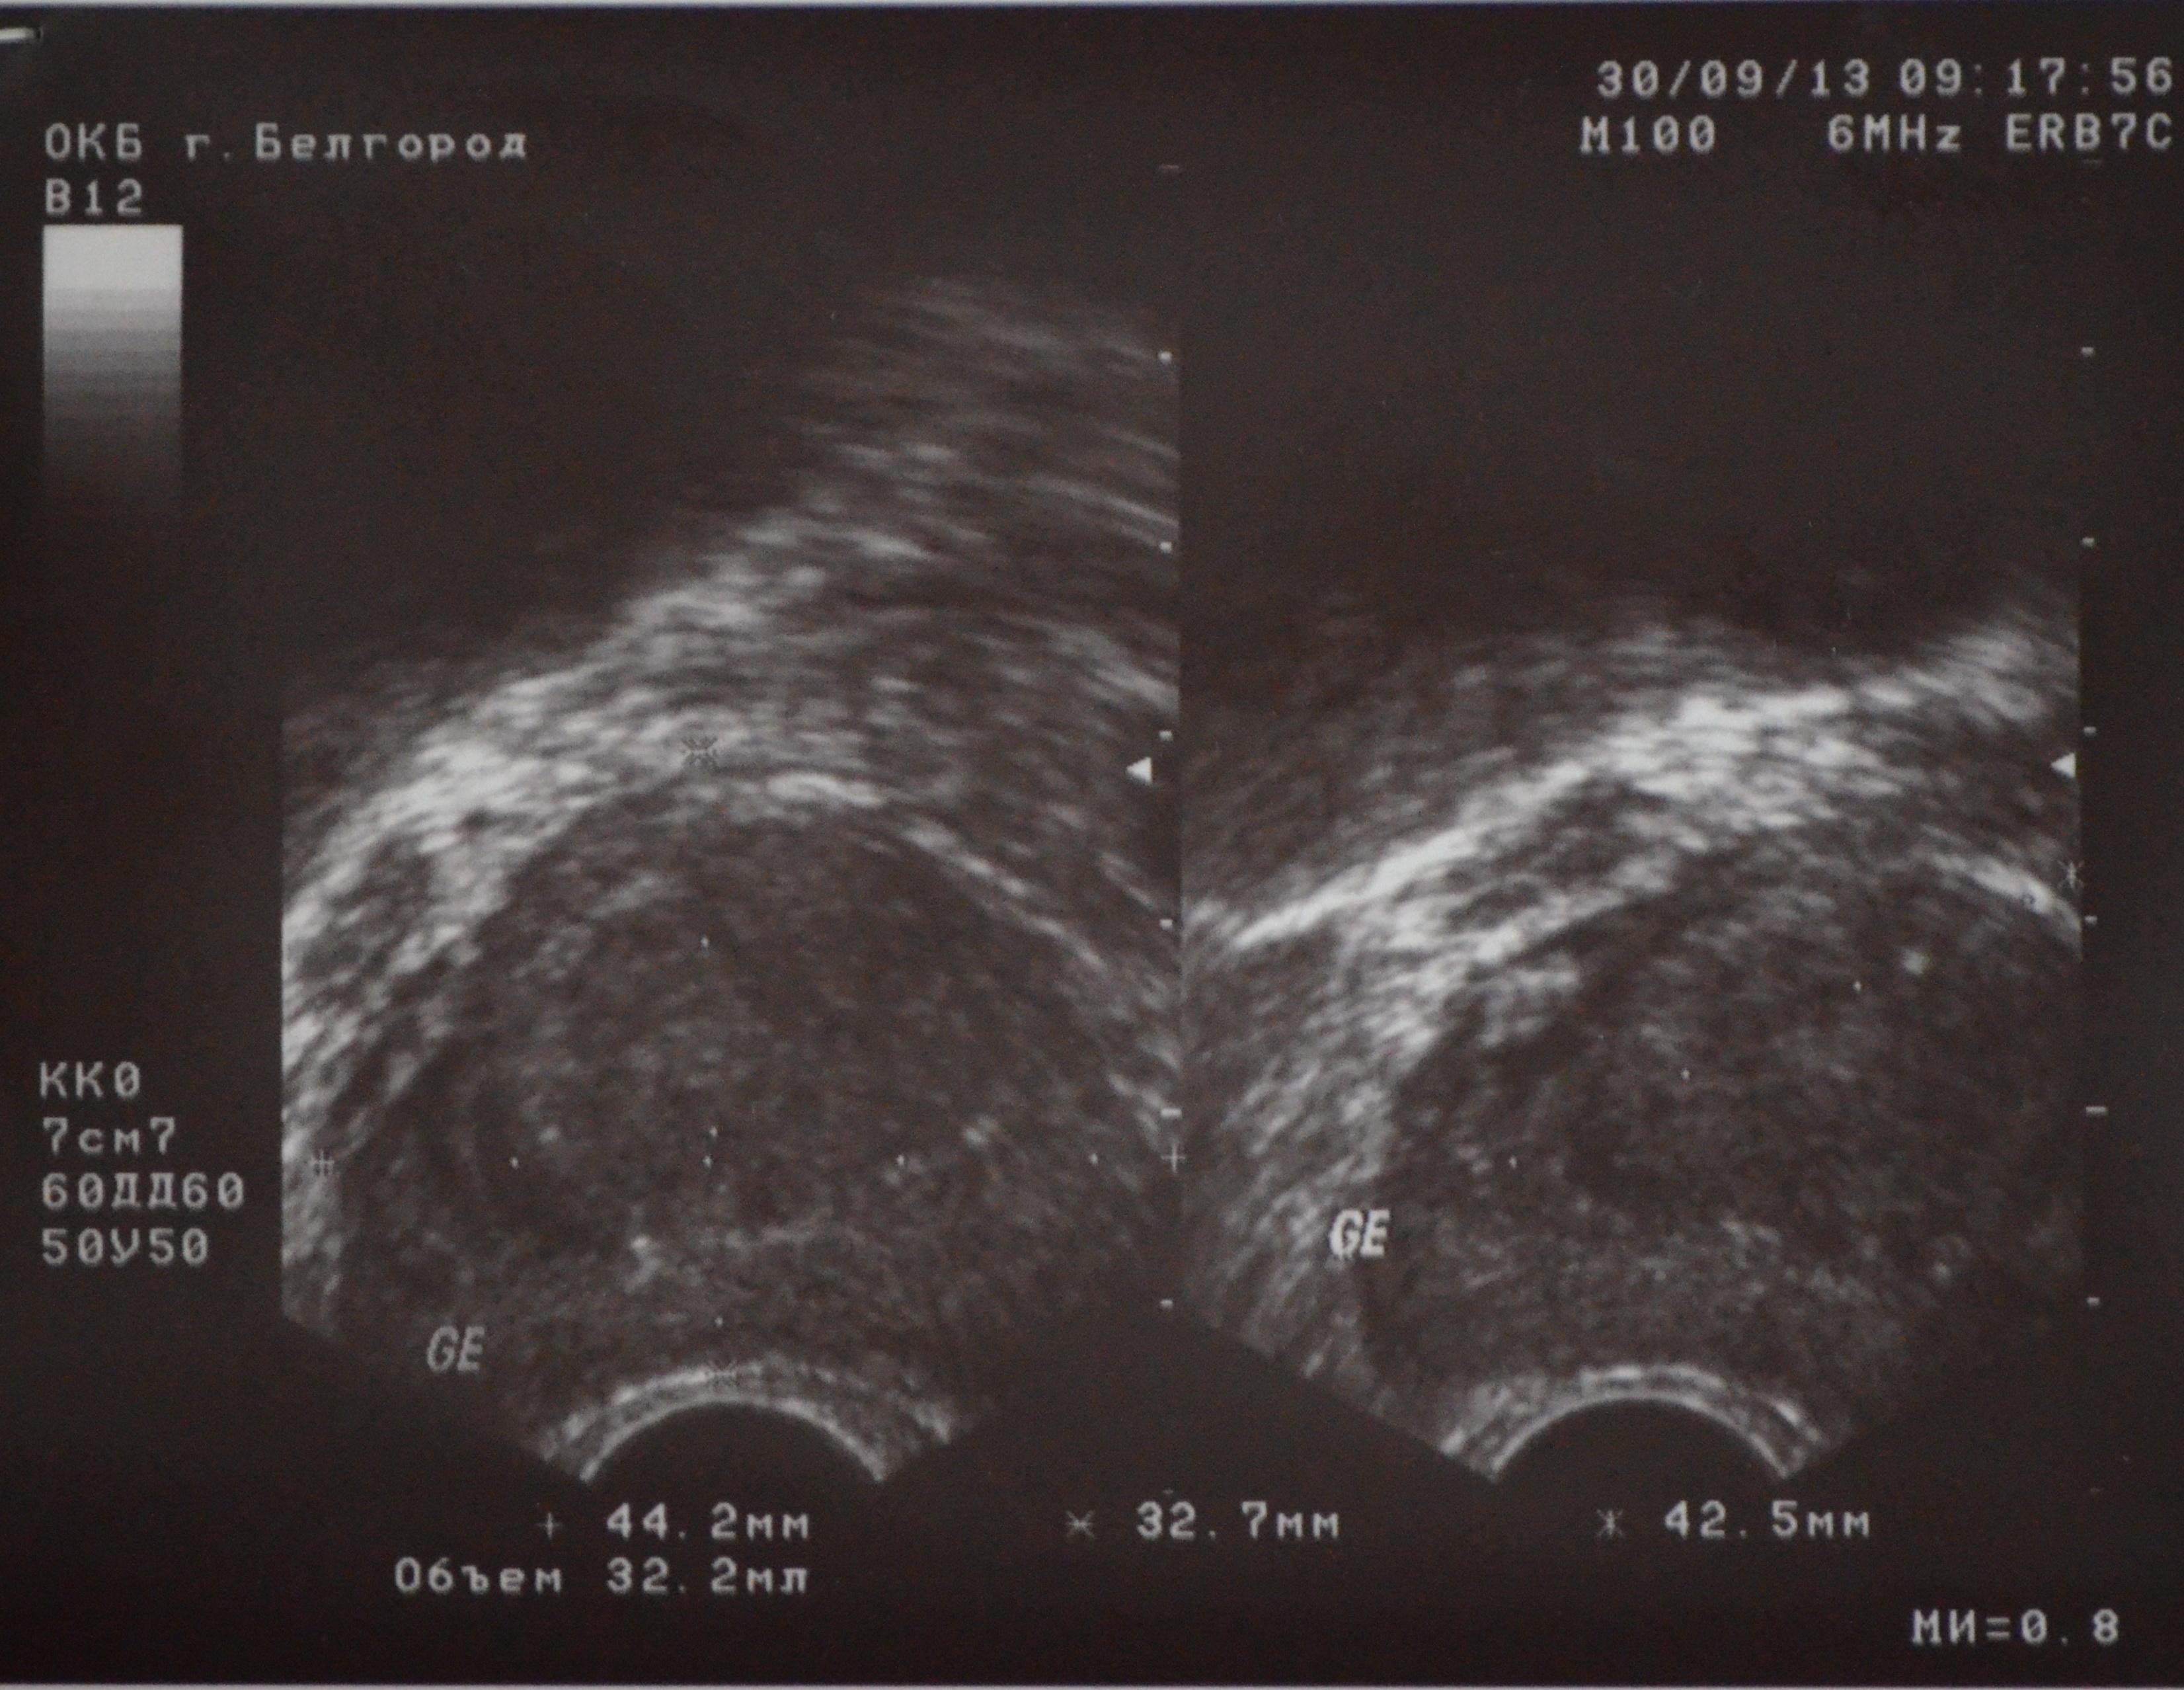

Данные трузи такие:

Предстательная железа – 44,2*32,7*42,5мм,(V – 32,2см3)

Контур – неровный

Эхогенность – средняя

Капсула – сохранена

Структура – неоднородная

Кальцинаты – единичные мелкие вдоль хирургической капсулы

Очаговые изменения: в периуретральных зонах образования общим размером 32*24мм

Семенные пузырьки: ПЗР – 9,0мм, симметричны

Акустическая плотность – не изменена

Содержимое – однородное

И почему размеры столь разбросаны, относительно узи? Может я не так понимаю 44,2-это толщина, 32,7-это ширина, а 42,5-это высота?

Прилагаю фото результатов.